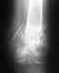

Сделала перевязку, и обезбаливающий, потом отвезли домой. Ето произошло около 7 недель назад. Я потом сама шодил на приём, так как болело сильно, сделали снимок, и там непоказало что трещина или перелом. Делала повязку тугую, но сеичас всё ещо есть опухоль, и временами она опухает по новои,. Что мне делать, ето доставляет мне неудобства, и боль. Помоги те мне пожауиста советом.Спасибо.P.S. У меня много ошибок, прошу прощения

Лучше показаться ортопеду. Возможно, есть какие-то незажившие повреждения в области голеностопного сустава. Из дополнительных исследований информативно MRI.